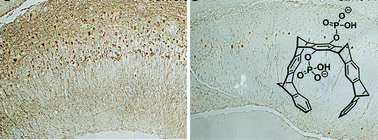

Molecular tweezers represent the first class of artificial receptor molecules that have made the way from a supramolecular host to a drug candidate with promising results in animal tests. Due to their unique structure, only lysine and arginine are well complexed with exquisite selectivity by a threading mechanism, which unites electrostatic, hydrophobic and dispersive attraction. However, tweezer design must avoid self-dimerization, self-inclusion and external guest binding. Moderate affinities of molecular tweezers towards sterically well accessible basic amino acids with fast on and off rates protect normal proteins from potential interference with their biological function. However, the early stages of abnormal Aβ, α-synuclein, and TTR assembly are redirected upon tweezer binding towards the generation of amorphous non-toxic materials that can be degraded by the intracellular and extracellular clearance mechanisms. Thus, specific host–guest chemistry between aggregation-prone proteins and lysine/arginine binders rescues cell viability and restores animal health in models of AD, PD, and TTR amyloidosis.